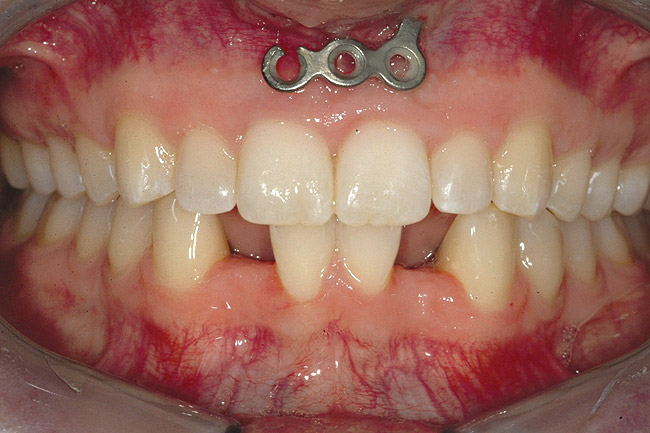

Fig 8 (and Fig 9). Teeth Nos. 5 and 12 were converted to Nos. 6 and 11, and Nos. 6 and 11 were converted to Nos. 7 and 10. Nos. 4 and 13 were enlarged. Note stability and absence of orthodontic relapse. Before-and-after smiles. Periodontist: Edward P. Allen, DDS, PhD. Prosthodontist: Robert R. Winter, DDS.

Figure 8

Fig 9 (and Fig 8). Teeth Nos. 5 and 12 were converted to Nos. 6 and 11, and Nos. 6 and 11 were converted to Nos. 7 and 10. Nos. 4 and 13 were enlarged. Note stability and absence of orthodontic relapse. Before-and-after smiles. Periodontist: Edward P. Allen, DDS, PhD. Prosthodontist: Robert R. Winter, DDS.

Figure 9